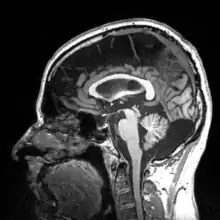

Sagittal view of a human brain through MRI

Paleoneurobiology revolves around the analysis of endocasts. Much of this analysis is focused on interpreting sulcal patterns, which is difficult because traces are often hardly recognizable, and there are no clear landmarks to use as reference points. Furthermore, the only clear reference plane is the sagittal plane one, which is marked by distinct cerebral asymmetries. Since the obtaining of clear data from fossil details is usually very difficult, much debate arises over interpretations. Experience is often an important factor in endocast analysis.[1] Therefore, a large portion of the field of paleoneurobiology arises out of developing more detailed procedures that increase the resolution and the reliability of interpretations.